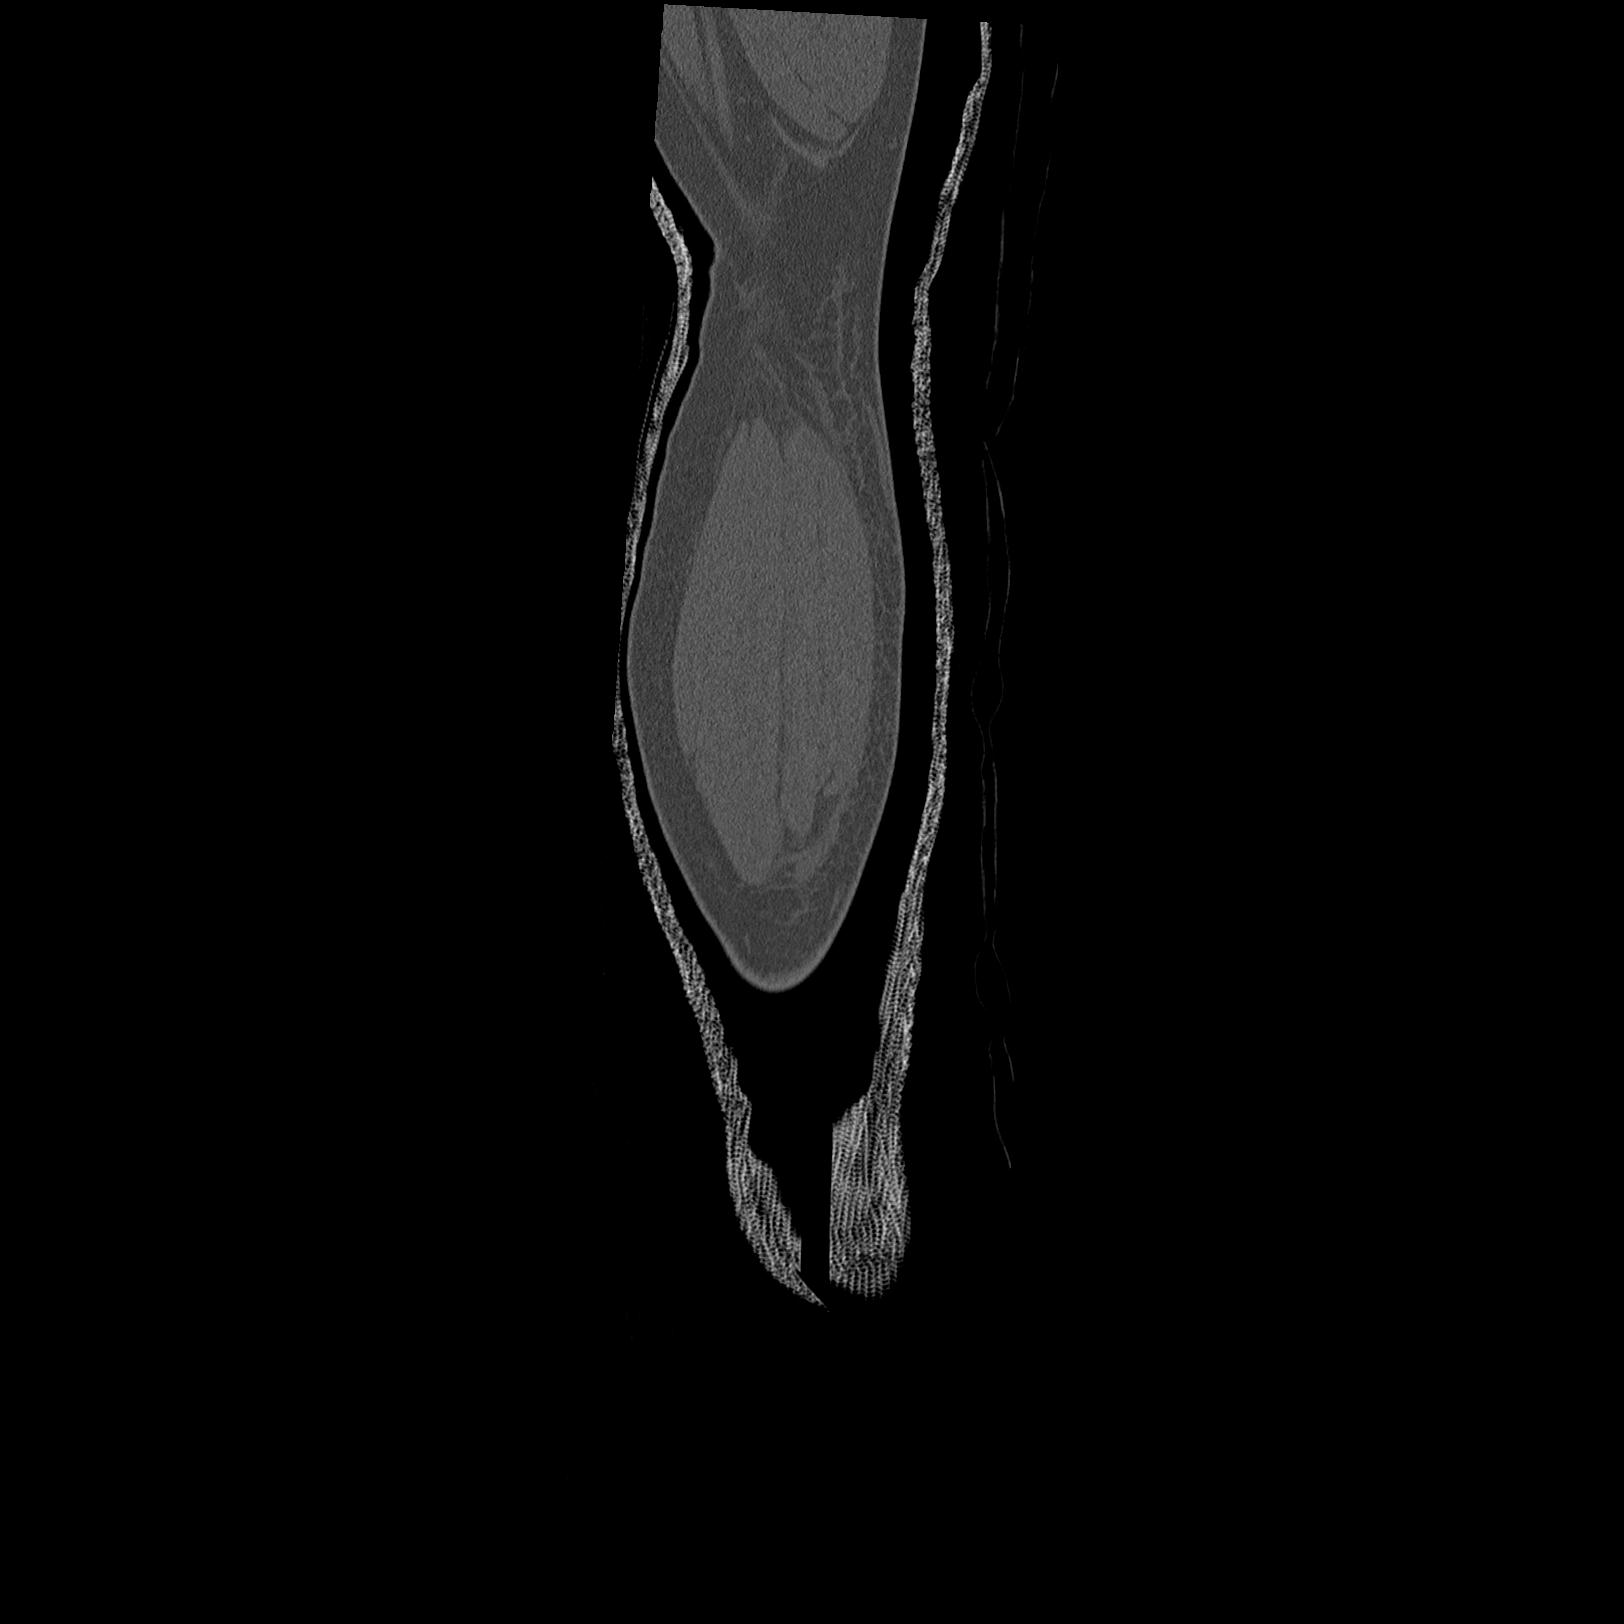

102803 1/12(キウスなし) 1/27 左下腿 4R 30歳女性 左脛骨軸内釘

110211 1/6 1/8 左前腕 4R 15歳男性 橈骨骨幹部骨折